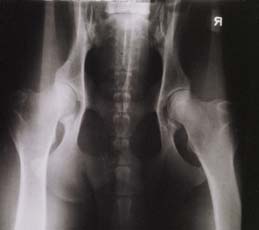

Hund mit HD-Grad B und sehr

lockeren Hüftgelenken in normaler Aufnahmetechnik: keine Luxation |

| Der selbe Hund in der

gehaltenen Aufnahme: Deutliche Subluxation der Femurköpfe. Distraktionsindex 0,50 rechts und 0,47 links |